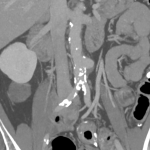

He underwent a CT scan which showed a 5 cm dilatation of his large artery in the abdomen called aorta (saccular infrarenal aortic aneurysm).